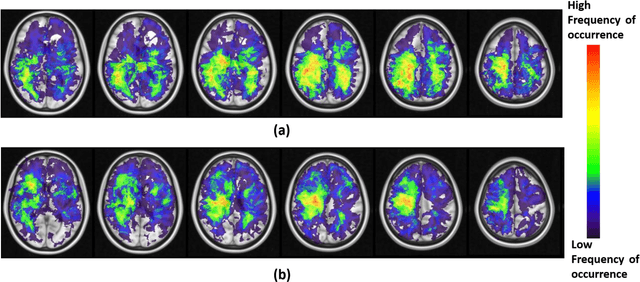

Abstract:A significant challenge in Glioblastoma (GBM) management is identifying pseudo-progression (PsP), a benign radiation-induced effect, from tumor recurrence, on routine imaging following conventional treatment. Previous studies have linked tumor lobar presence and laterality to GBM outcomes, suggesting that disease etiology and progression in GBM may be impacted by tumor location. Hence, in this feasibility study, we seek to investigate the following question: Can tumor location on treatment-na\"ive MRI provide early cues regarding likelihood of a patient developing pseudo-progression versus tumor recurrence? In this study, 74 pre-treatment Glioblastoma MRI scans with PsP (33) and tumor recurrence (41) were analyzed. First, enhancing lesion on Gd-T1w MRI and peri-lesional hyperintensities on T2w/FLAIR were segmented by experts and then registered to a brain atlas. Using patients from the two phenotypes, we construct two atlases by quantifying frequency of occurrence of enhancing lesion and peri-lesion hyperintensities, by averaging voxel intensities across the population. Analysis of differential involvement was then performed to compute voxel-wise significant differences (p-value<0.05) across the atlases. Statistically significant clusters were finally mapped to a structural atlas to provide anatomic localization of their location. Our results demonstrate that patients with tumor recurrence showed prominence of their initial tumor in the parietal lobe, while patients with PsP showed a multi-focal distribution of the initial tumor in the frontal and temporal lobes, insula, and putamen. These preliminary results suggest that lateralization of pre-treatment lesions towards certain anatomical areas of the brain may allow to provide early cues regarding assessing likelihood of occurrence of pseudo-progression from tumor recurrence on MRI scans.